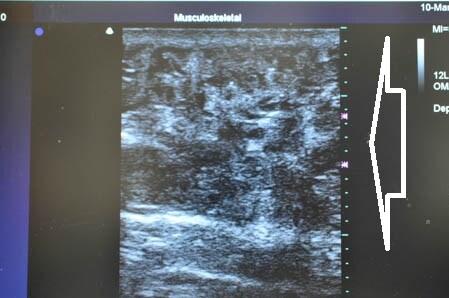

左の腰も見ておきましょう。

↓ ↓ ↓